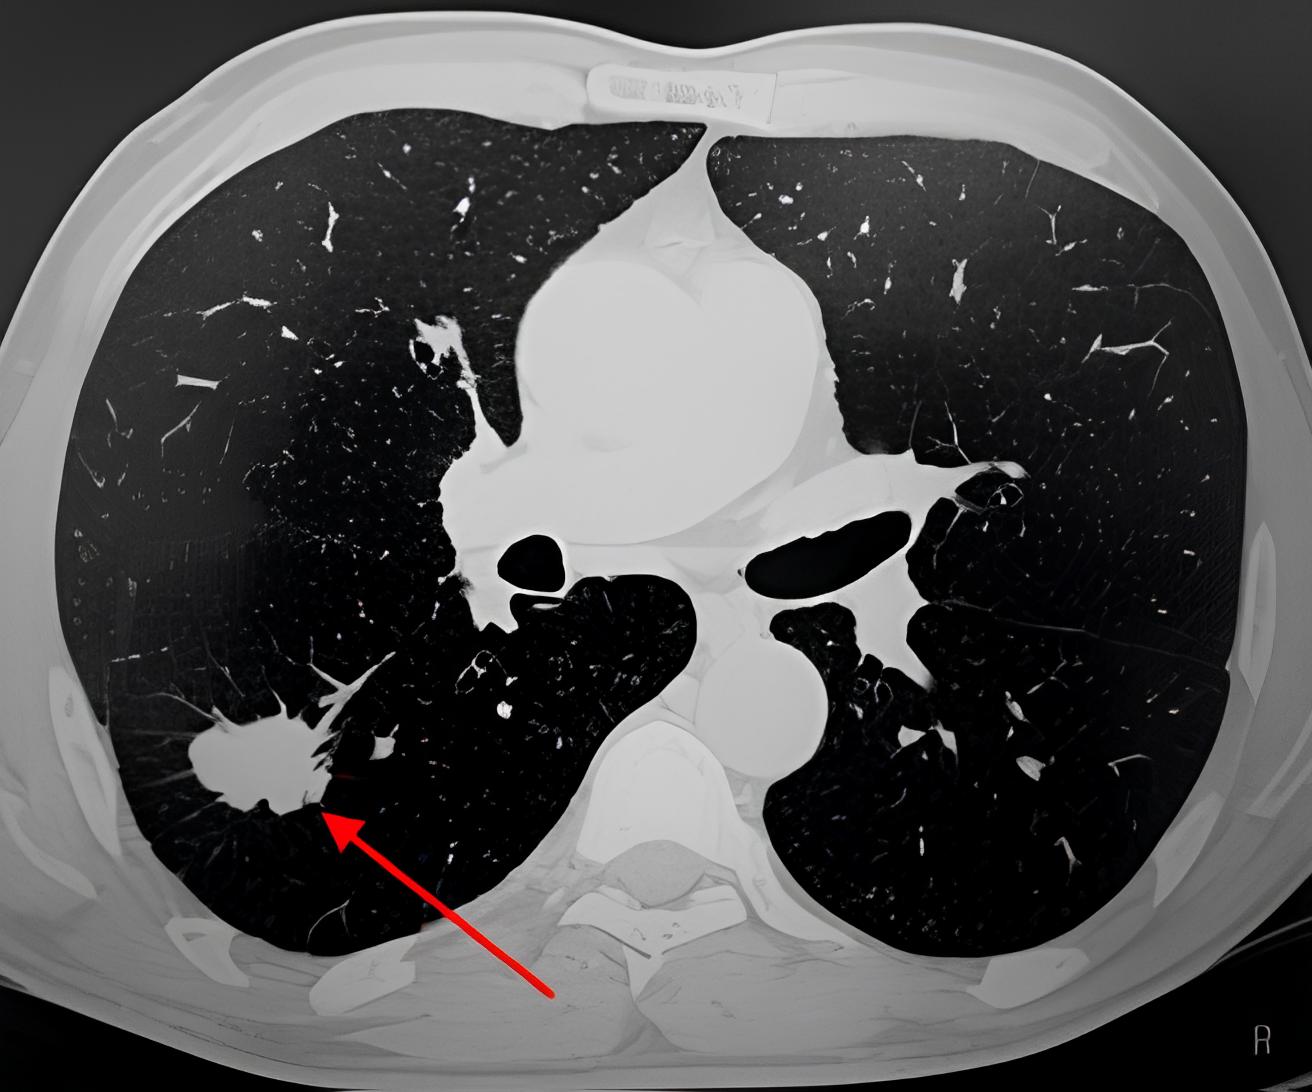

Форум после кт

Форум после кт 80 фото